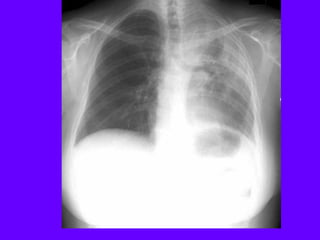

Consolidation Left Lower Lobe

Density in left lower lung field

Left heart silhouette intact

Loss of diaphragmatic silhouette

No shift of mediastinum

Pneumatocele

One diaphragm only visible

Lobar density

Oblique fissure not significantly

shifted